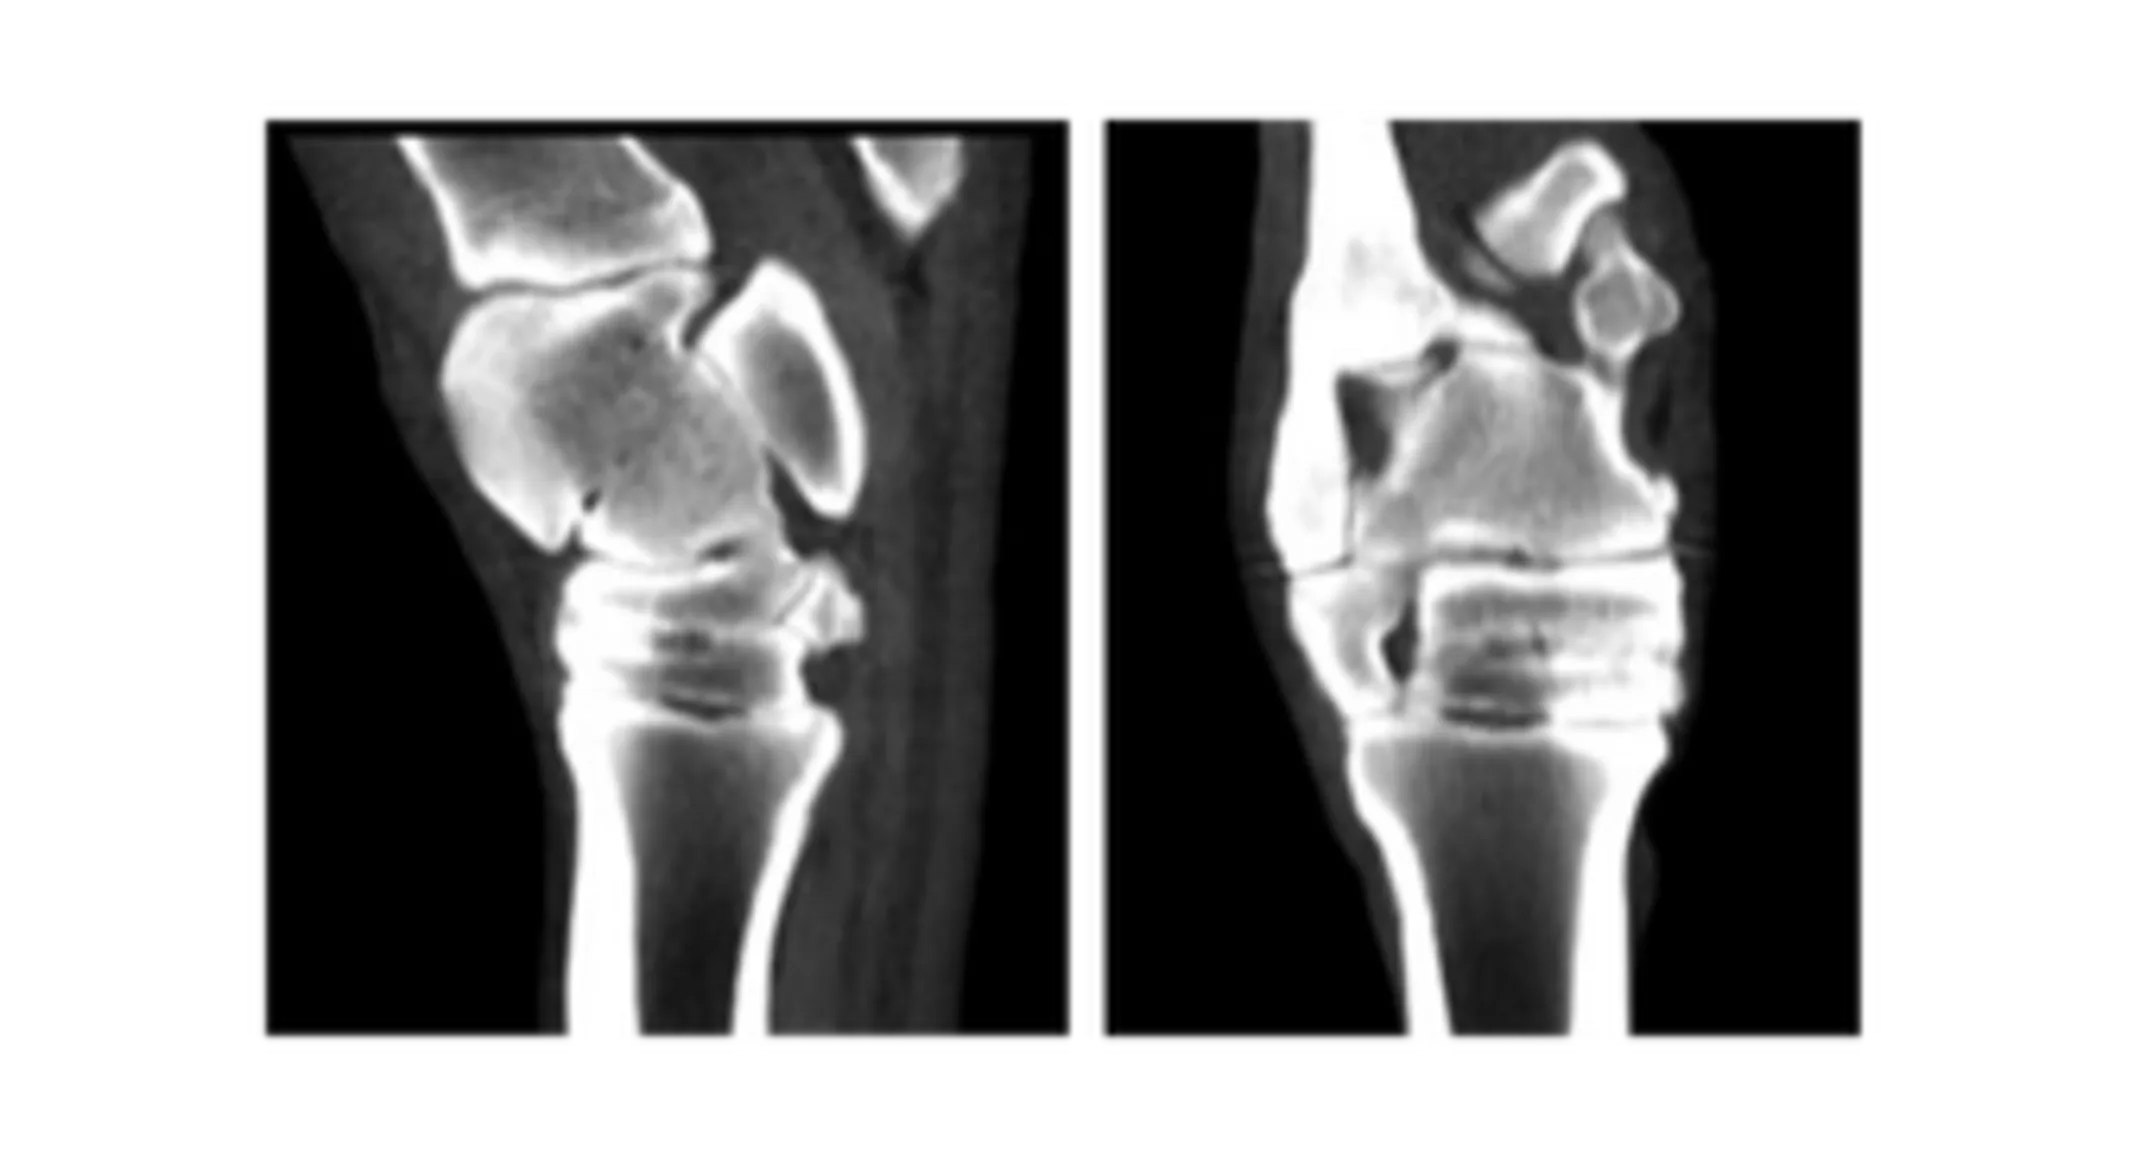

Case #4 – Proximal Hind Limb CT

History: 8-year-old Quarter Horse mare presented for advanced imaging of the tarsus/proximal metatarsus. The mare had a history of a RH lameness that responds to intra-articular therapy of the distal tarsal joints, but only for a short period of time.

Diagnosis: Marked osteoarthritis and partial ankylosis of the distal intertarsal joint. Recommended surgical ankylosis due to progression of disease and lack of response to therapy.